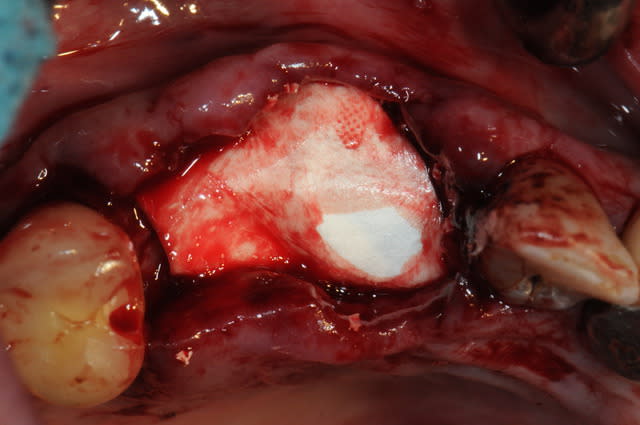

ici une extraction d'une 13 avec implantation de 14 et 13 direct.

14 pas beaucoup d'os en vestibulaire , donc expansion avec ostéotomes et ROG plus tard.

13 implantation dans une cavité+++, l'implant tient peu il baigne dans le bio-os.

il doit être recouvert d'une membrane (pour 14 surtout).

mais, j'ai de craintes de ne pas avoir suffisamment d'étanchéité.

c'est le cas, car une fois les sutures terminées, il me reste la membrane qui est exposée.

je prélève un petit lambeau au palais, l'incision se fait à l'opposé du centre du greffon de façon à avoir un biseau partout.

je passe un fil de suture avant de suturer. c'est trop difficile de travailler un truc fin comme du papier.

je replace le greffon au dessus de la membrane et il vient tout naturellement se plaquer à celle ci.

je précise que c'est un fil de suture avec une aiguille à chaque extrémité du fil.